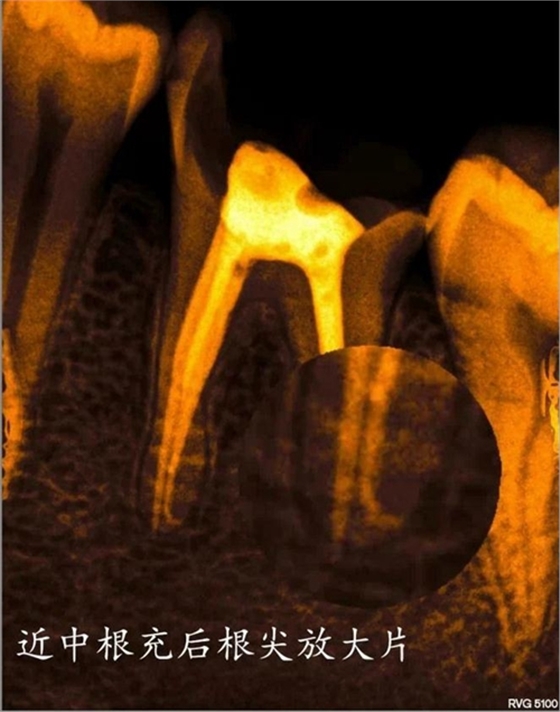

部分病例: